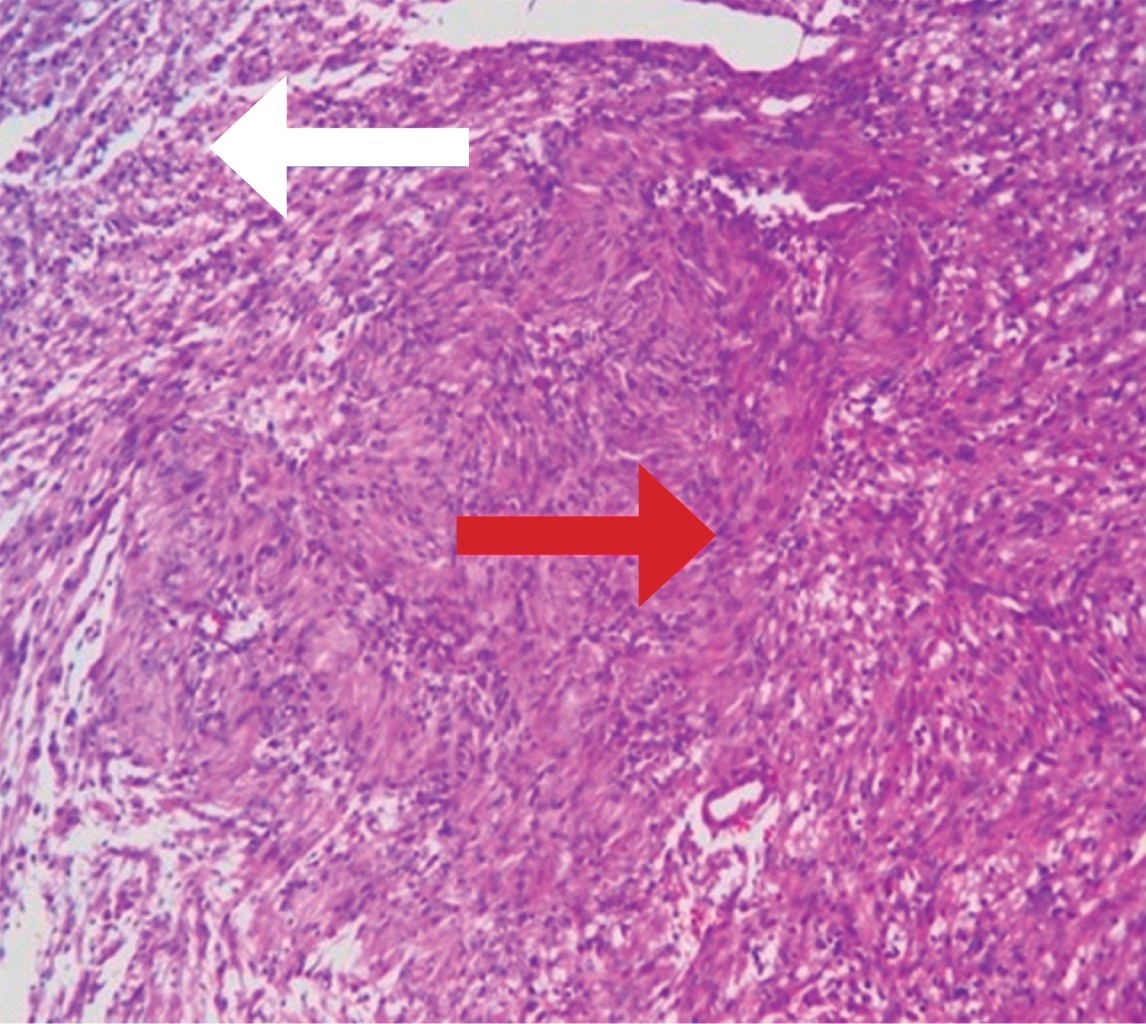

Microscópicos: lesión neoplásica benigna constituida por células fusiformes con dos patrones morfológicos Antoni A de mayor celularidad y Antoni B hipocelular (Figura 4), con áreas mixoides y presencia de cuerpos de Verocay.

Figura 4